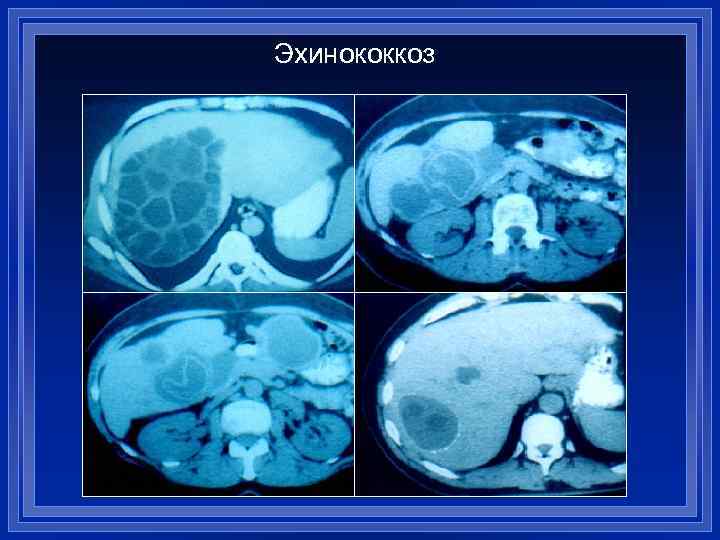

Эхинококкоз